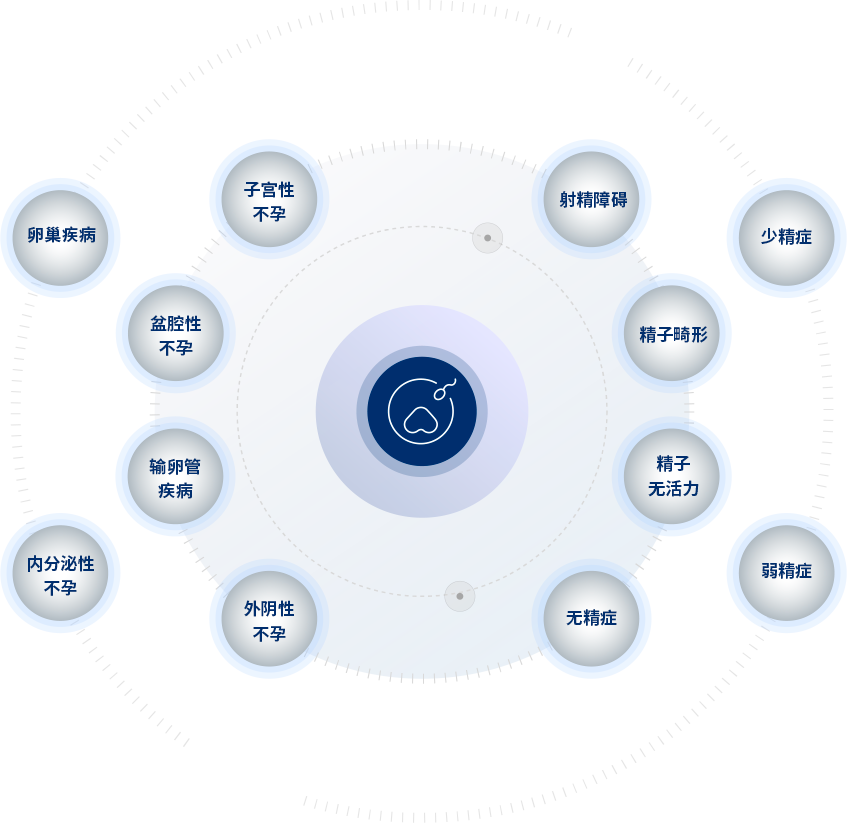

“一(yi)站式(shi)”助孕服務(wu)

“一(yi)站式(shi)”助孕服務(wu)

生(sheng)殖中(zhong)心開展(zhan)各種男、女不孕不育症的(de)診斷(duan)與治療,4D超聲子(zi)宮輸(shu)卵筦(guan)造(zao)影術(shù)、陰道超聲檢(jian)測(ce)排(pai)卵、染色體(ti)遺傳(chuan)學(xué)檢(jian)查等(deng)醫(yī)療服務(wu)項(xiang)目(mu)。